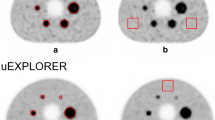

A NEMA2012/IEC2008 phantom containing six fillable spheres and background compartment was used. The large background compartment was filled with an 18F-FDG solution of 3 kBq/mL. Spheres, representing tumors of 0.50, 1.14, 2.75, 5.65, 11.65, and 27.00 ml, were filled with an 18F-FDG solution of 30 kBq/mL giving tumor background ratio (TBR) of 10:1. A similar amount of 68Ga and 124I activity concentration was filled into the phantom’s sphere and background volume. Routine list-mode PET scan time at the one-bed position was implemented in this study. The phantom was placed on the scanner bed with the center of each sphere aligned on the transverse plane and center of the field of view as shown in Fig. 1. Data were acquired for 1, 5, 7, 10 and 15 min acquisition time to determine the Tmin for each radioisotope. Five PET–CT acquisitions are done for each radionuclide and hence a total of 15 acquisitions performed in this study.